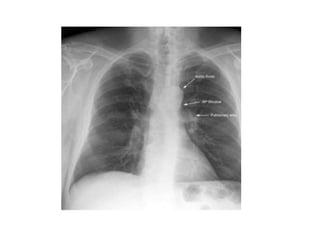

This document provides an overview of interpreting chest x-rays and identifies several key factors. It discusses the importance of inspiration, penetration, and rotation in obtaining a technically quality radiograph. It also outlines different views of chest x-rays including PA, AP, and lateral views. Finally, it identifies several anatomical structures that should be evaluated when interpreting a chest x-ray such as the lungs, heart, diaphragm, bones, and soft tissues.